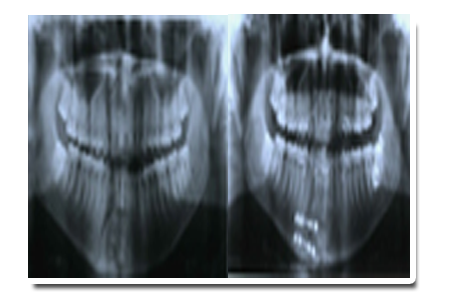

X-ray view of plating surgery done in fracture lower jaws as shown below: